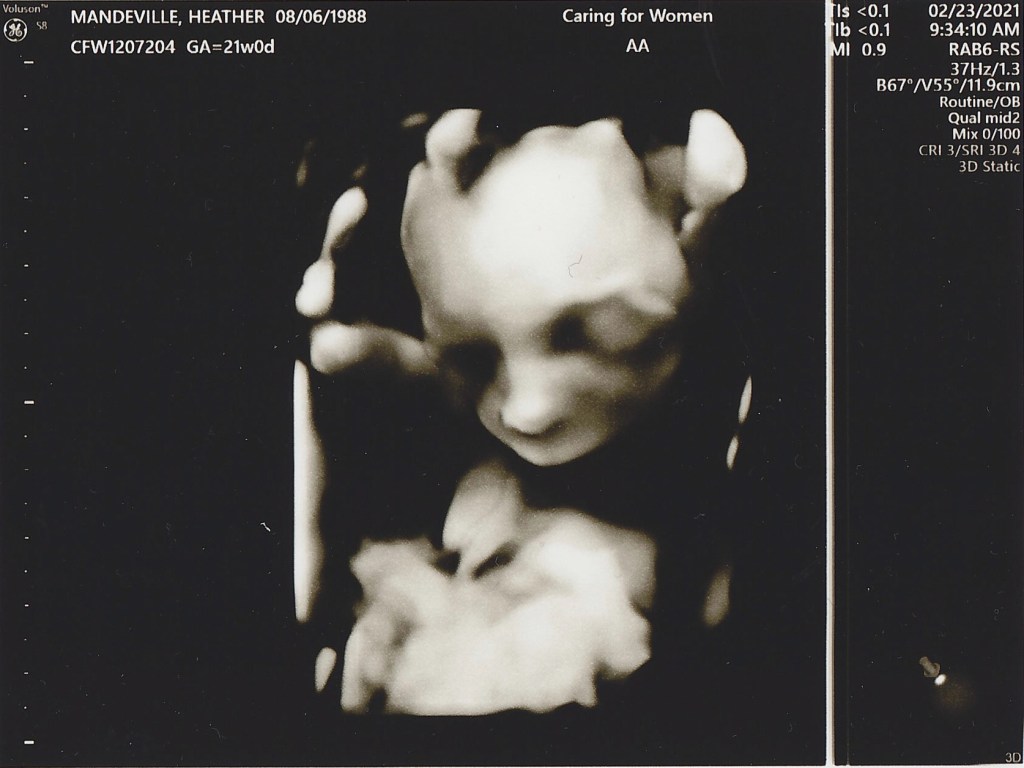

20 week sonogram

IT’S A BOY!! We found out today we are having a boy and we could not be more excited! Everything is looking good, Heather and the baby are healthy and he is progressing as expected. Now we get to start really planning to welcome him into this world, so many things to do in the next 20 weeks!